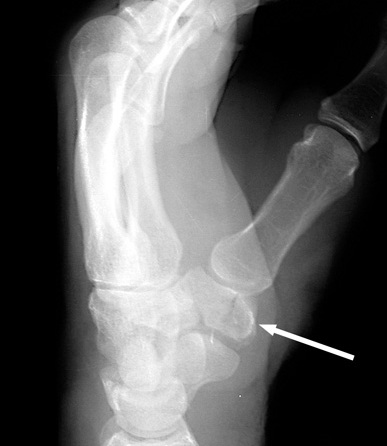

Trapezium fracture

- Best seen on 20-degree pronated oblique view